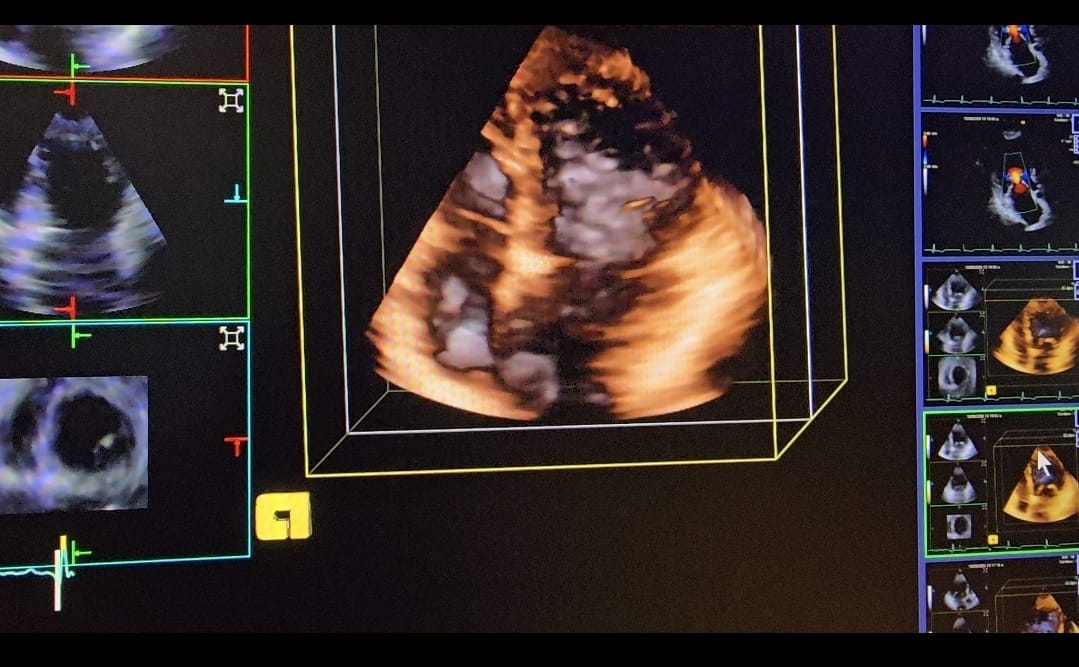

Evaluación cardiológica completa

Diagnóstico y tratamiento de enfermedades del corazón y vasos sanguíneos. Prevención de enfermedades cardiovasculares. Cardiología Clínica.

ECG. Holter. MAPA. Ecocardiograma doppler color. Ecodoppler vascular periferico. Ecocardiograma fetal . Ecoestres con ejercicio.